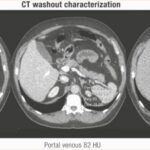

TC con contraste técnica de lavado (wash out)

Aproximadamente el 30% de los adenomas suprarrenales benignos no contienen grandes cantidades de grasa y tienen un valor de atenuación de >10 UH (es decir, adenomas bajos en lípidos); estas lesiones no se pueden caracterizar de manera confiable en tomografía sin contraste debido a una densidad superpuesta con lesiones malignas y feocromocitomas.(14, 15)

Para las lesiones con un valor de atenuación de >10 UH, se requiere una evaluación adicional y no hay un consenso claro con respecto a cuál es la mejor imagen de segunda línea para estos pacientes. Como conclusión, en un estudio realizado por Seo y colaboradores(16) se manifestó que la resonancia magnética es equivalente a la tomografía para caracterizar los adenomas que miden 20 UH o menos en la tomografía sin contraste. Sin embargo, la resonancia magnética es inferior a la tomografía para los adenomas que miden más de 20 UH debido a la disminución de la sensibilidad de la RM. En la práctica institucional realizar una tomografía computarizada dedicada al protocolo de lavado suprarrenal como siguiente prueba es más preciso para caracterizar los adenomas hipolipídicos que la resonancia magnética, aunque, como ha demostrado un metaanálisis reciente, hay necesidad de más estudios para optimizar esta técnica, ya que hay una variabilidad significativa en los protocolos de escaneo y los tiempos descritos y las sensibilidades y especificidades.

Los estudios de lavado consisten en imágenes de TC realizadas antes y en dos puntos de tiempo después de la administración de contraste intravenoso (normalmente, las imágenes se realizan a los 60-90 segundos y 10 o 15 minutos después del contraste) sin evidencia clara sobre el mejor intervalo de tiempo para el último punto de tiempo.(17) Los adenomas por lo general contrastan rápidamente y muestran un lavado rápido del contraste intravenoso, a diferencia d las lesiones suprarrenales malignas, que por lo general contrastan rápidamente pero demuestran un lavado más lento del medio de contraste.

Valores absolutos de lavado de >60% se obtienen con la siguiente fórmula: (UH contraste temprano – UH contraste retardado)/( UH contraste temprano – UH sin contraste) × 100% sugieren un adenoma benigno.(14,18)

El lavado relativo se puede calcular cuando la TC sin contraste no está disponible (UH contraste temprano – UH retardada)/ UH contraste temprano × 100%.

Los valores de > 40 % sugieren un adenoma benigno.(15,18,19)

Sin embargo, Angelelli y colaboradores evaluaron la precisión del lavado en el diagnóstico diferencial entre adenomas y no adenomas y comparar los resultados obtenidos en tomografías computarizadas retrasadas a los 5, 10 y 15 minutos; llegaron a concluir que la evaluación de los valores de TC realizadas a los 5, 10 y 15 minutos proporciona resultados de diagnóstico comparables. Por lo tanto, se prefieren las tomografías computarizadas realizadas a 5 minutos, ya que reducen el tiempo de examen y la incomodidad del paciente.

Sin embargo, consideraron solo 50 casos, por lo que se requieren estudios prospectivos más grandes para validar el rendimiento del lavado de TC de contraste en pacientes con incidentalomas. También se requiere precaución porque, si bien los feocromocitomas por lo general muestran un lavado de contraste lento, ocasionalmente pueden imitar adenomas benignos de lípidos al mostrar un lavado rápido. Por lo tanto, después de la discusión del equipo multidisciplinario (MDT), si todavía hay una sospecha con respecto a una lesión con una UH indeterminada, se debe solicitar un escaneo adicional para garantizar que no haya más crecimiento.